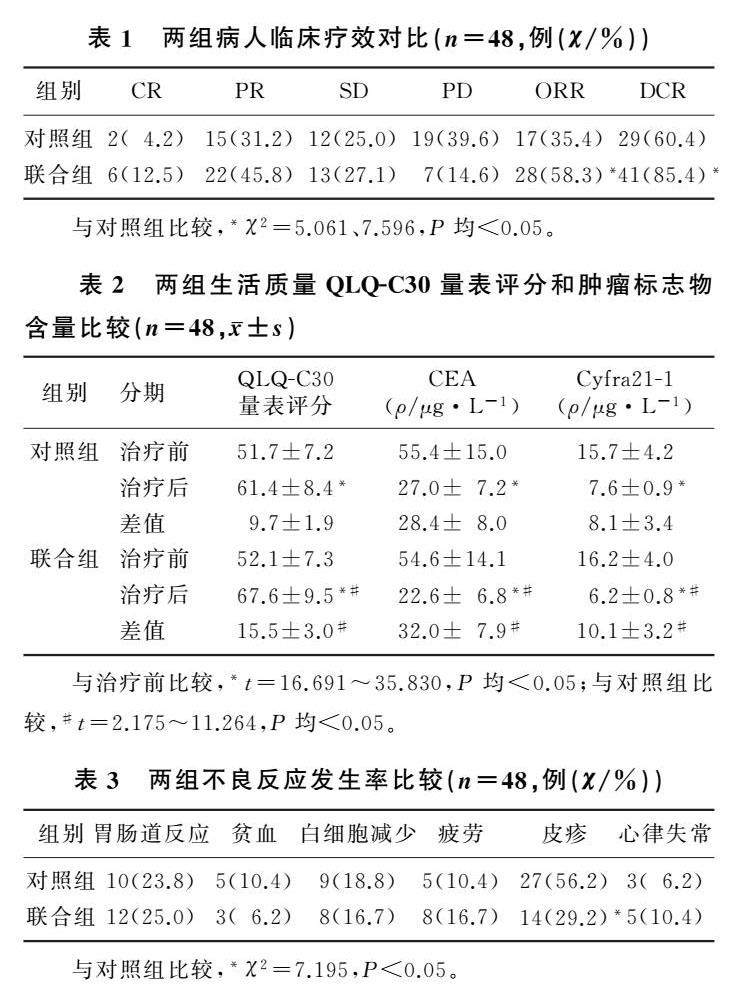

论著 | 艾瑞卡联合恩度对晚期NSCLC临床疗效及肿瘤标志物影响

论著 | 艾瑞卡联合恩度对晚期NSCLC临床疗效及肿瘤标志物影响